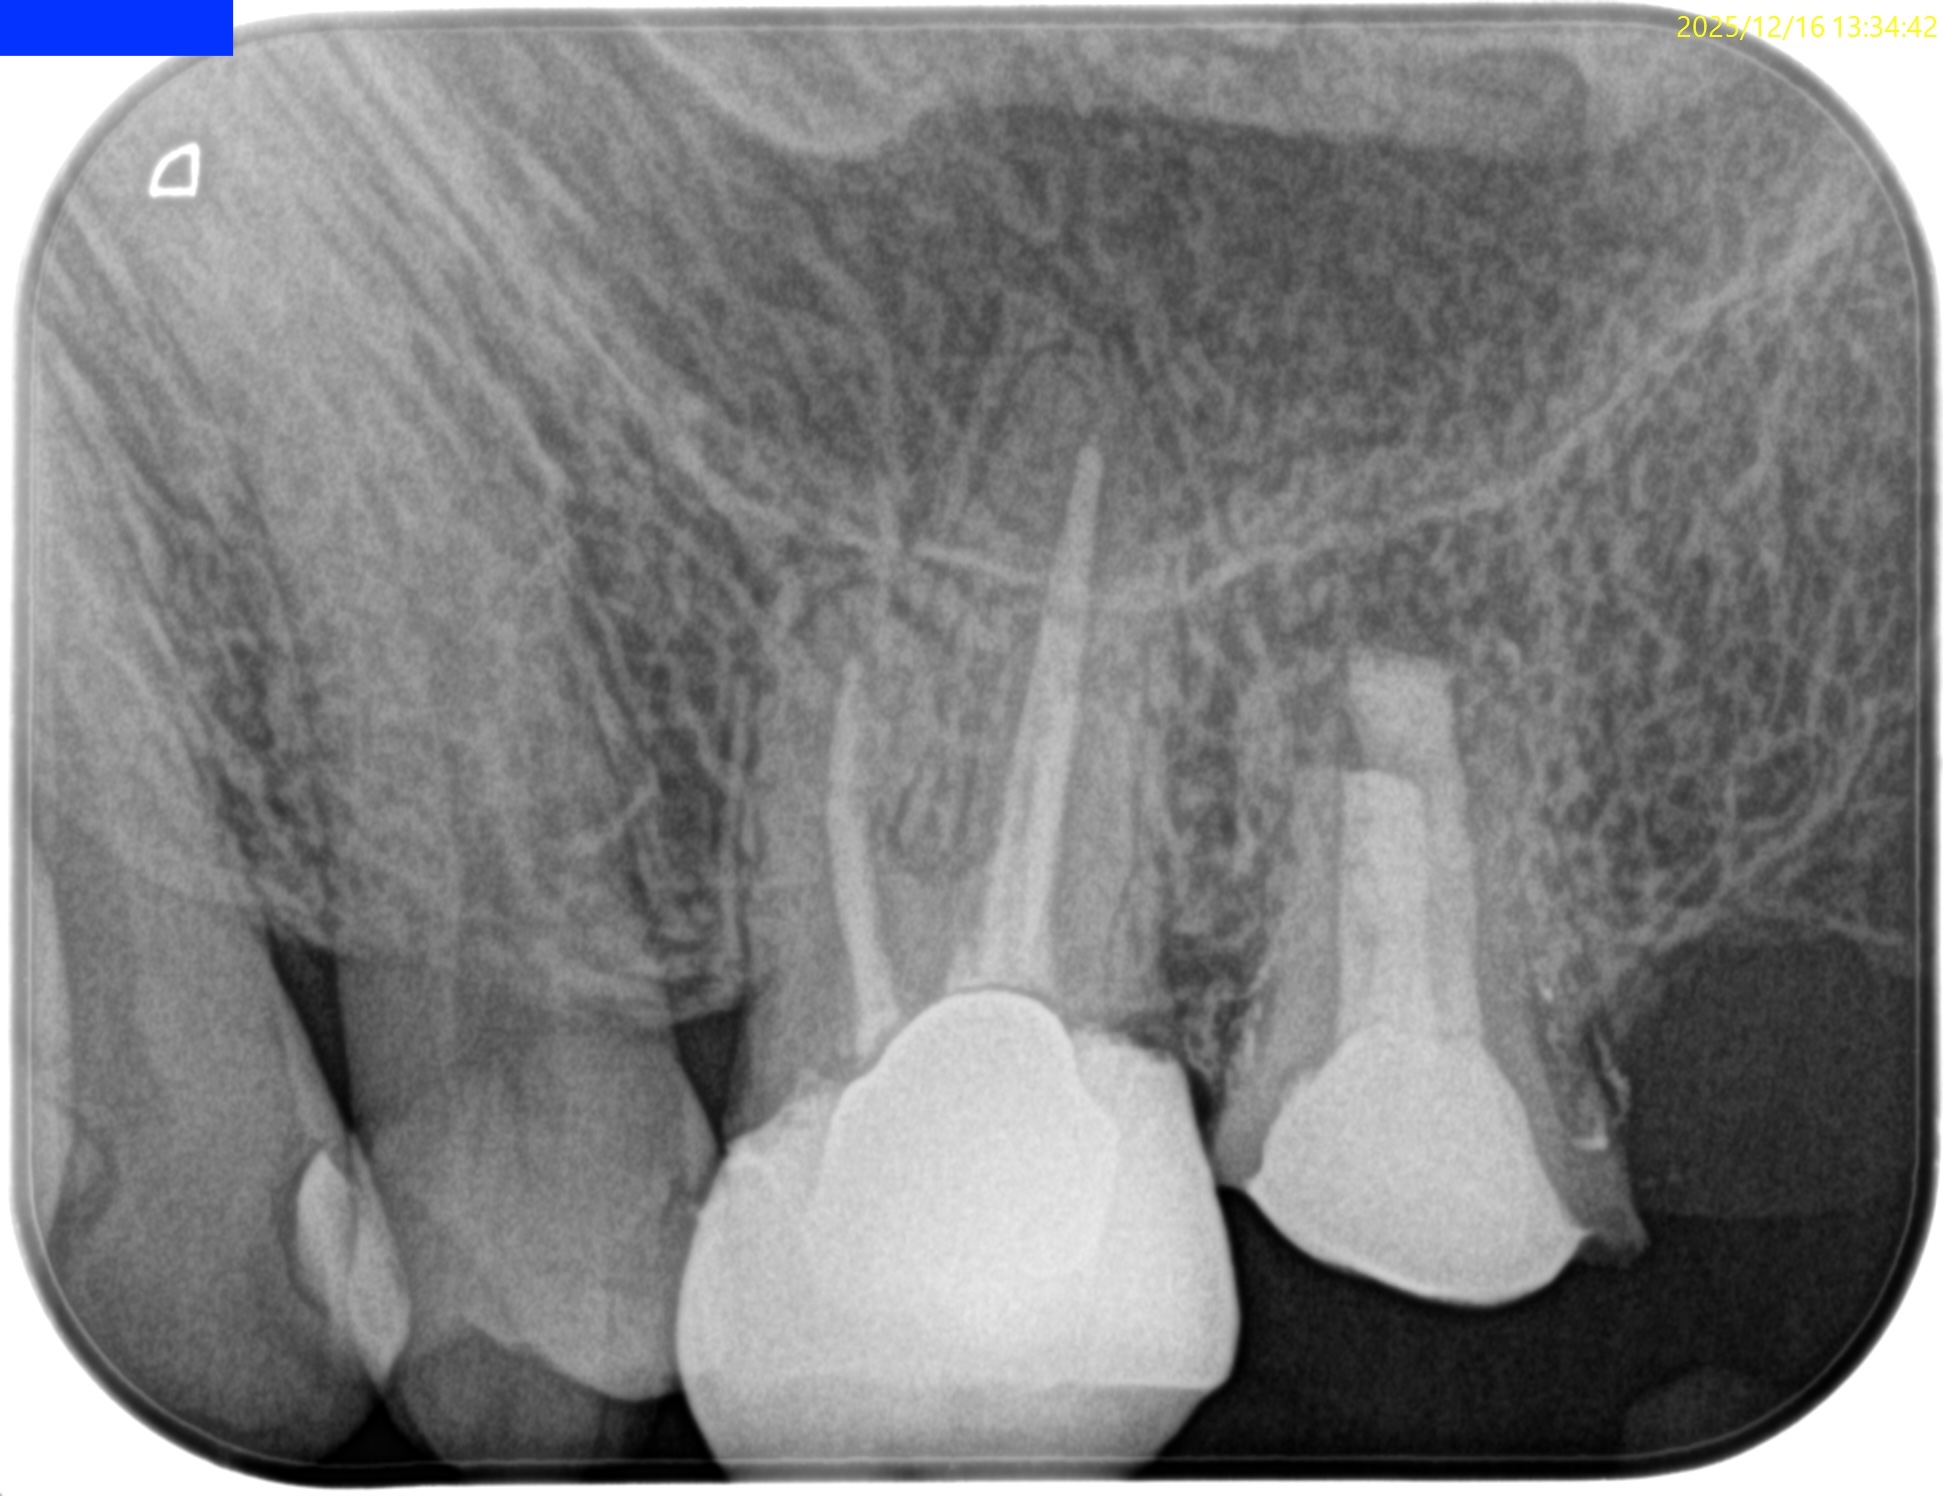

抜歯にいつも以上に時間がかかった。

このように歯質があまりない場合はペリオトームを使用し、歯周組織を全集剥がす必要があるだろう。

そしてダイヤモンド鉗子は残根用の物を使用した。

抜歯窩に残根がないことを確認し、ここから口腔外作業に入る。

破折がないか?確認した。

破折がないのでここからApicoectomy作業である。

術後にPAを撮影した。

問題はないだろう。